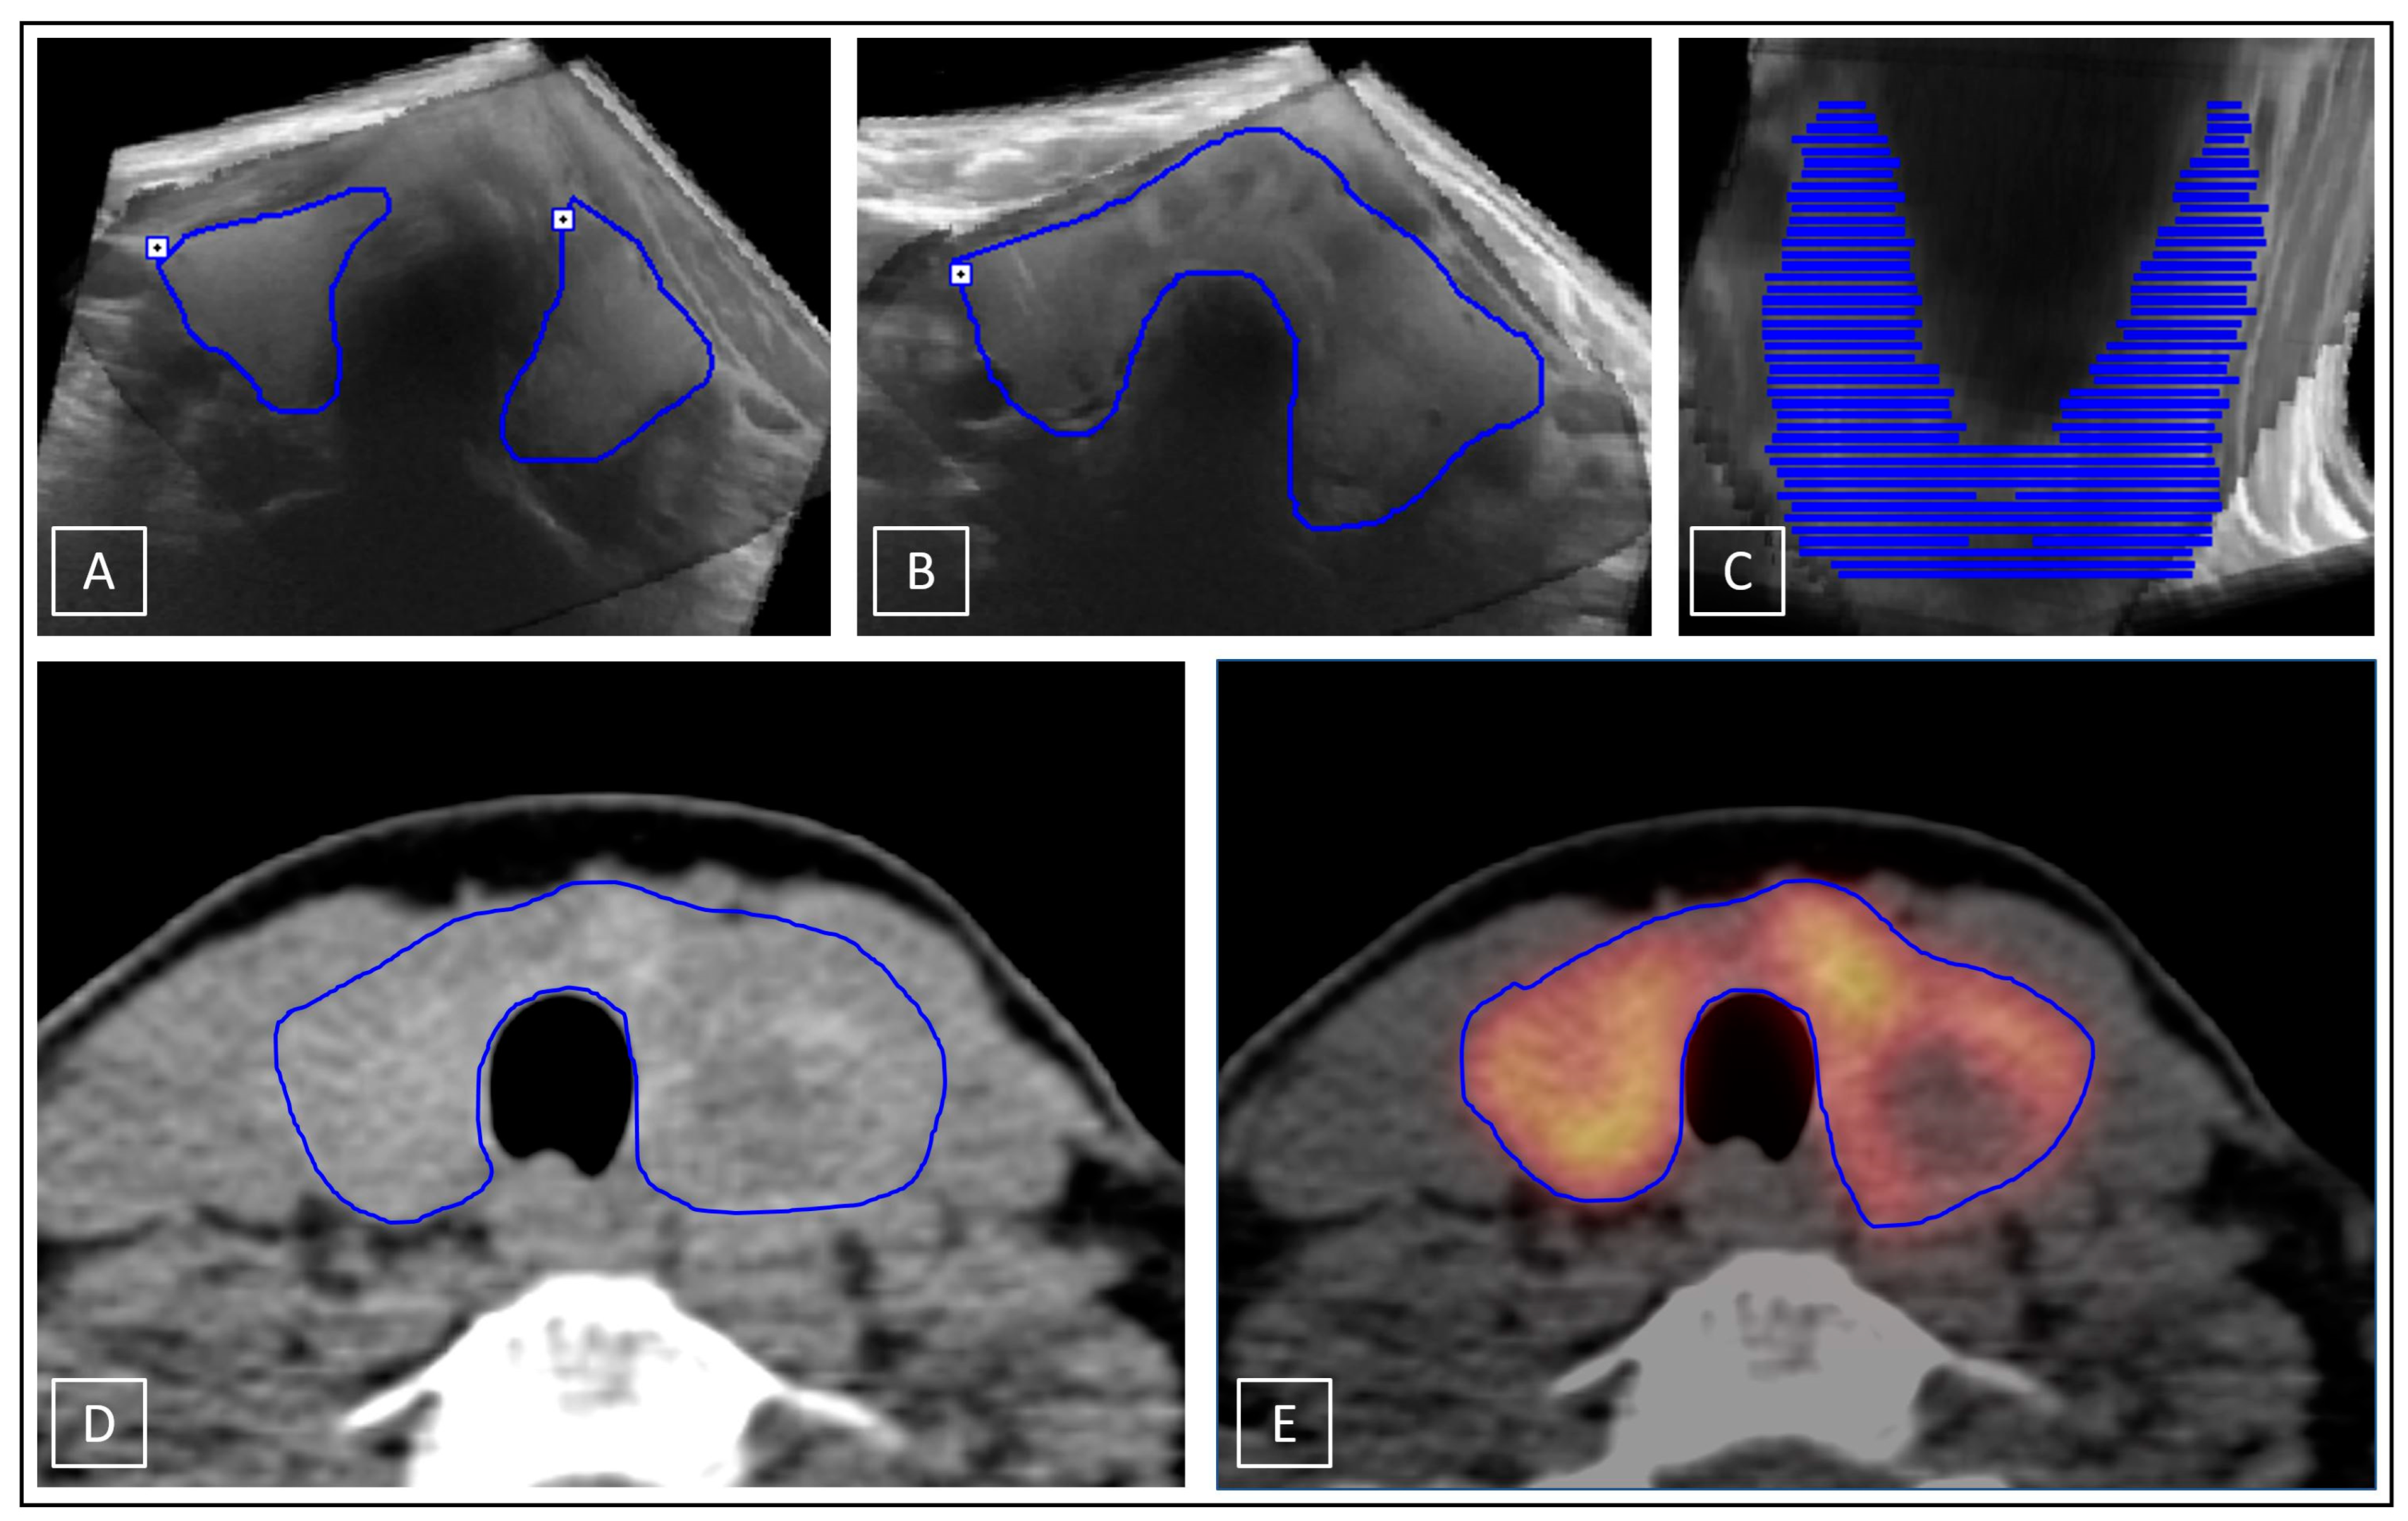

Two different methods were used to measure the thyroid volumes. ConUS data were evaluated via the ellipsoid model (conUS-EM): V = (4/3) * π * (largest cranial-caudal diameter/2) * (largest anterior-posterior diameter/2) * (orthograde medial-lateral diameter/2) [24]. Volume determination of the stitched 3D-US data sets were performed by multiple manually drawn segmental contouring applications (MC) in transverse plane in PMOD software according to the organ boarders (3DsnUS-MC, 3DmsUS-MC). The same method was also used to measure the thyroid volumes on I-124-PET/CT scans in Syngo.via software (PET/CT-MC), which defined the reference standard values. To avoid prejudiced biases, determination of the reference was performed only after the measurements of the thyroid volumes on the several US data sets. For further comparative analyses, the CT scans alone were additionally evaluated in Syngo.via software using both the MC and EM methods (CT-EM, CT-MC). ConUS-EM and CT-EM applications are demonstrated in Figure 4.

MC applications on 3D-US (3DsnUS-MC and 3DmsUS-MC), CT (CT-MC), and I-124-PET/CT (PET/CT-MC) are shown in Figure 5.

Figure 5.

Multiple manually drawn segmental contouring applications (MC) exemplarily demonstrated on a stitched 3DsnUS data set in PMOD software; manually outlined thyroid gland (blue lines) in transverse plane without (A) and with isthmus (B); representation of all drawn contours on coronal view (C). MC method applied on CT (D) and I-124-PET/CT (E) scans in Syngo.via software; manually outlined thyroid gland on a representative transverse plane.